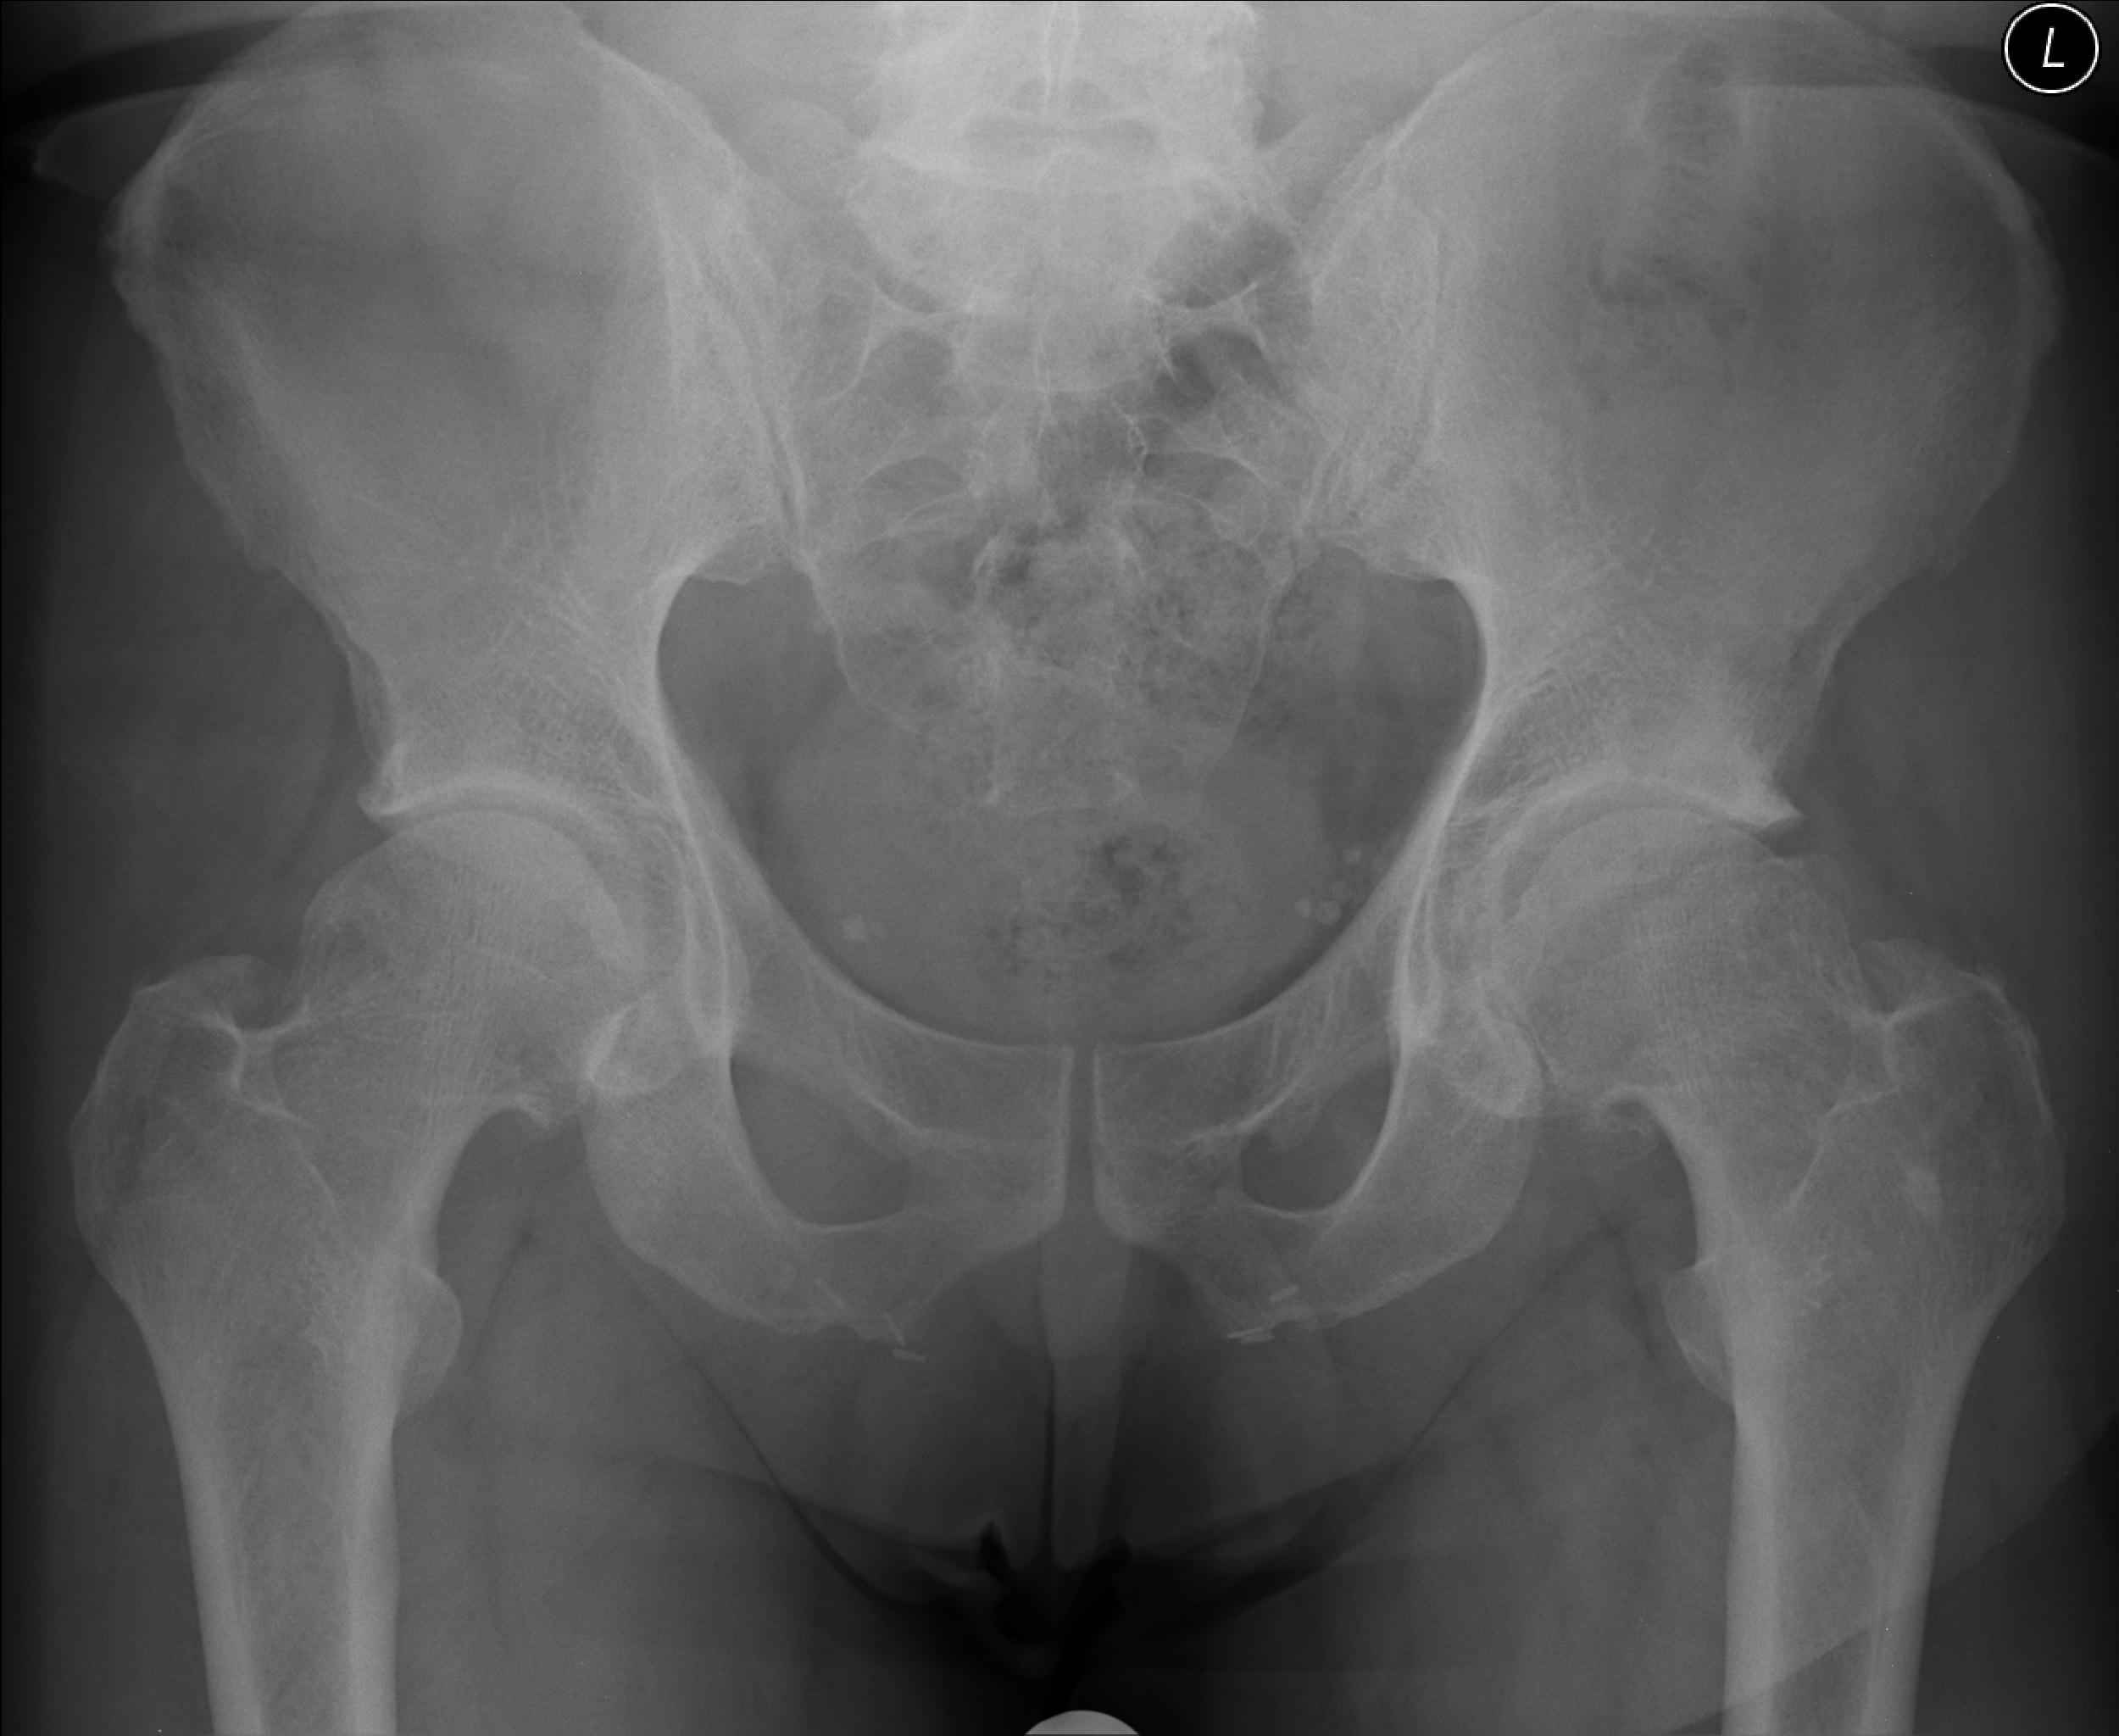

A Normal Joint X-Ray Image

This is what A Normal Joint X-ray looks like